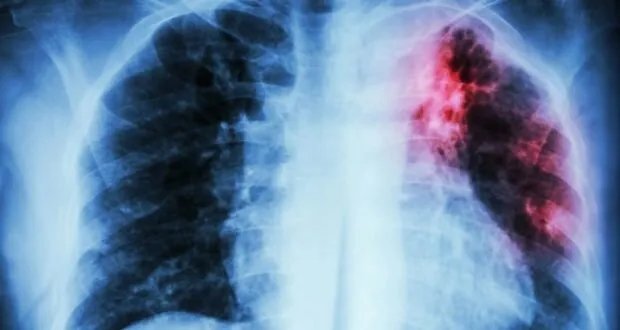

الجدير بالذكر أن السل مرض يمكن الوقاية منه وعلاجه، وينجم عن بكتيريا تصيب الرئتين في أغلب الأحيان، وينتقل عن طريق الهواء عندما يسعل أو يعطس أو يبصق الأشخاص المصابون.